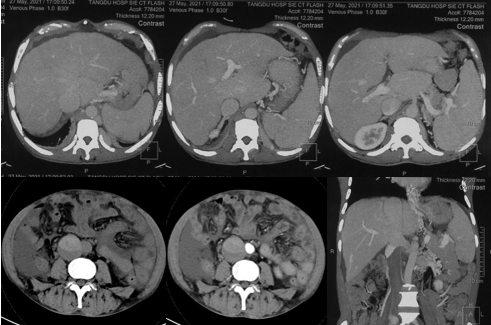

6月20日,患者及家屬懷揣著忐忑的心情來到西安國際醫(yī)學(xué)中心醫(yī)院找到韓國宏教授,韓教授詢問病情后閱患者外院CT片,明確診斷布加綜合征,同時發(fā)現(xiàn)了一個新的問題,在詢問病史時了解到患者近一周雙下肢乏力伴腫脹明顯加重,遂立即安排了急診CT,證實下腔靜脈內(nèi)急性血栓形成!

6月22日,在韓國宏教授的帶領(lǐng)下,患者于消化介入診療中心行下腔靜脈開通術(shù)。術(shù)中可見:下腔靜脈全段擴張,膜性閉塞,腎靜脈平面以下可見血栓形成并伴有粗大的側(cè)枝靜脈,遂對狹窄段球囊擴張并植入支架,術(shù)后下腔靜脈血流通暢,側(cè)枝消失。術(shù)后第2天,患者腹壁靜脈曲張幾乎消失不見,走路也輕快了許多。明明只是薄薄的一層膜,為什么開通起來這么難?韓教授指出,盡管布加綜合征介入開通技術(shù)已使創(chuàng)傷降到了最低,但受到患者個體差異及醫(yī)療水平參差不齊的限制,仍有可能出現(xiàn)嚴(yán)重的并發(fā)癥,主要包括:心包積血、縱隔血腫、心包填塞甚至下腔靜脈撕裂引起的大出血等。而其發(fā)生率與術(shù)者的操作熟練程度及經(jīng)驗有很大的關(guān)系。